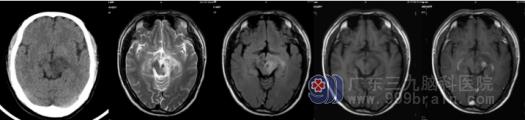

图1 患者男,41岁,全身游走痛,右侧肢体偏瘫、左侧面瘫1年,加重1月;长期有口腔溃疡病史。影像学检查中脑左侧为主病灶,CT检查呈低密度,MRI表现病灶为长T1长T2异常信号,FLAIR序列高信号,存在红核豁免征,增强明显强化。